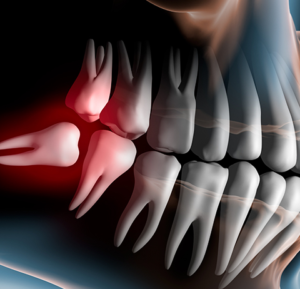

Chuẩn bị răng và lấy dấu: Trước tiên Nha sĩ sẽ kiểm tra răng và có thể cần phải chụp X-ray để kiểm tra xem tủy răng còn tốt không hoặc nếu răng bị nhiễm trùng thì cần phải lấy tủy trước khi tiến hành làm mão răng. Trước khi mài răng, một vài trường hợp bệnh nhân cần phải được tiêm thuốc tê để giảm ê buốt, sau đó răng sẽ được mài hết cả mặt ngoài, mặt bên và mặt lưỡi của răng, lượng mài nhiều hay ít sẽ tùy thuộc vào loại chất liệu mão răng nào mà bệnh nhân đã chọn lựa. Nếu trong trường hợp răng cần bọc mão mất nhiều do mẻ hay sâu, thì Nha Sĩ sẽ tái tạo răng với chất liệu trám răng, tái tạo thành một cùi răng trước khi bọc mão bên ngoài. Sau khi mài răng thành những cùi răng hoàn chỉnh, Nha Sĩ sẽ lấy dấu răng gửi vể Lab để tiến hành làm mão. Trong thời gian chờ mão răng Nha Sĩ sẽ gắn mão tạm cho bệnh nhân để đảm bão tính thẩm mỹ.